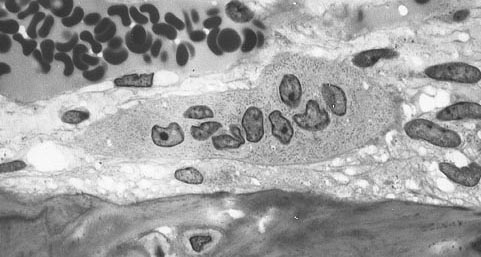

Působíci mechanismus ve všech případech osteoporózy je nesoulad mezi kostní resorpcí (absorbcí buněk do krevního oběhu) a kostní formací. Ve zdravé kosti, remodelace matrixu je konstantní, až do 10 procent kostní hmoty může podstupovat remodelaci kdykoli. Proces probíhá v kostních mnohobuňkových jednotkách (bone multicellular units - BMU), které poprvé popsali v roce 1963 vědci Frost a Thomas. Osteoklasty asistují transkripšním faktorem PU.1 na degradaci kostního matrixu, zatímco osteoblasty kostní matrix obnovují. Nízká kostní hustota pak může nastat, když osteoklasty degradují kostní matrix rychleji než osteoblasty kost zpevňují.